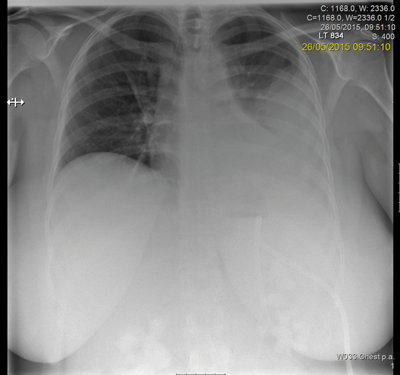

Following discussion at an X-ray meeting and a nephrology opinion, a left-sided percutaneous nephrolithotomy (PCNL) was performed in the prone position. Two tracts were placed by the urologist into the mid and upper portion of the kidney, clearing a reasonable volume and the patient was left with two nephrostomy tubes. The patient developed a postoperative reactive pleural effusion and chest infection requiring a chest drain. A prone CT revealed no radiological evidence of a pleural injury.

- Prone CT is useful for imaging the pleura in the postoperative phase.

- Morbid obesity is now an accepted part of treating stone disease. In female patients the subcutaneous adipose tissue often falls to one side in the prone position.